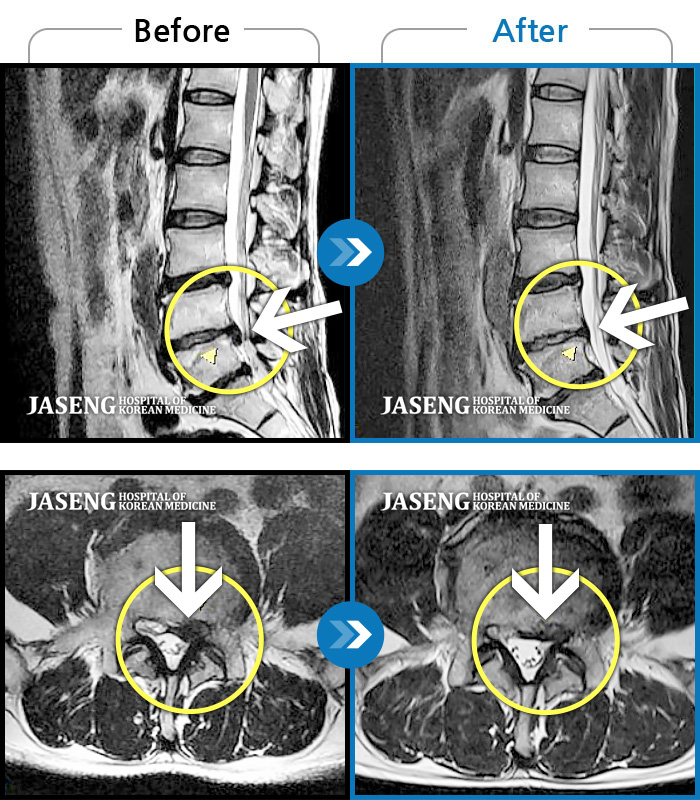

허리디스크

광주 · 장영우 원장

양측 허리부터 골반 묵직한 통증, 좌측 다리 외측까지 이어지는 당기는 통증으로 내원하셨습니다.

촬영시기

2503.04.01 ~ 2509.11.01